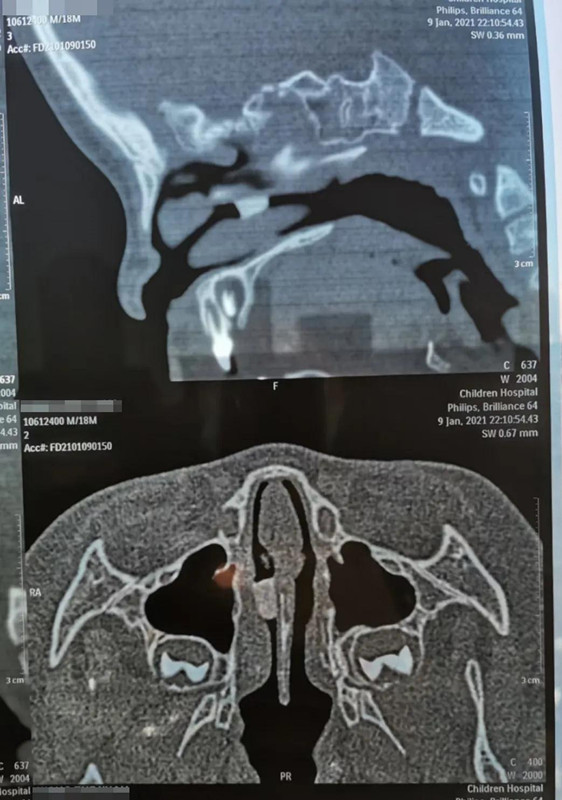

1月9日晚10点多,在夜深人安睡的时候,18个月男宝帅帅(化名)哭闹着被妈妈抱进德州扑克游戏网 就诊。妈妈说,晚上5点多,帅帅打碎了瓷鸭子玩具,偷偷把瓷鸭子嘴塞进鼻子里。经鼻腔三维CT重建,发现异物在右侧鼻腔较深位置,需次日全麻下手术取出。

取出8mm长异物